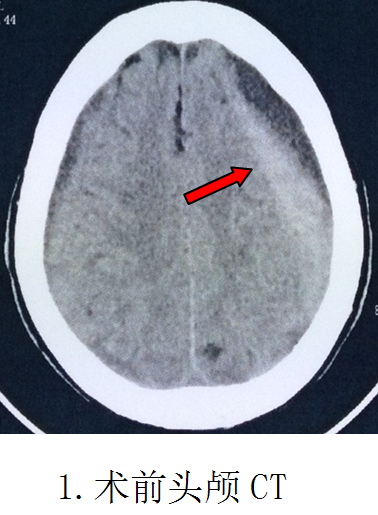

阿婆是在8天前因頭痛查因住進(jìn)醫(yī)院的。當(dāng)時(shí)頭痛、精神差伴右側(cè)肢體乏力1周,頭部CT檢查確診“左側(cè)額顳頂巨大慢性硬腦膜下血腫”,量約100多毫升。追問(wèn)阿婆1個(gè)月前有頭部外傷史。醫(yī)生建議手術(shù)治療。但是阿婆已經(jīng)98歲高齡了,家屬擔(dān)心無(wú)法挺過(guò)手術(shù)關(guān)。醫(yī)學(xué)常規(guī)認(rèn)為,超過(guò)70歲以及70毫升以上的顱內(nèi)血腫,手術(shù)是必須慎重的。阿婆98歲100多毫升的血腫,對(duì)于外科醫(yī)生是一個(gè)考驗(yàn)。這也是我院神經(jīng)外科至今遇到最高齡的一位手術(shù)患者了。如果在前幾年,對(duì)于阿婆的手術(shù),我們也是猶豫的。

第二天即實(shí)施手術(shù),在局部麻醉清醒狀態(tài)下,順利實(shí)施了微創(chuàng)手術(shù)“雙管硬通道微創(chuàng)鉆孔沖洗引流術(shù)”,頭皮只有兩個(gè)0.3厘米直徑的點(diǎn)狀鉆孔穿刺損傷,術(shù)中沖洗出血腫100多毫升,整個(gè)手術(shù)時(shí)間僅需30分鐘。復(fù)查CT血腫完全清除,手術(shù)成功。當(dāng)天晚上病人精神明顯好轉(zhuǎn),偏癱的右手即能抬起來(lái)跟醫(yī)生握手。第5天下床行走,偏癱肢體完全康復(fù),取得立竿見(jiàn)影的效果。第8天順利出院。